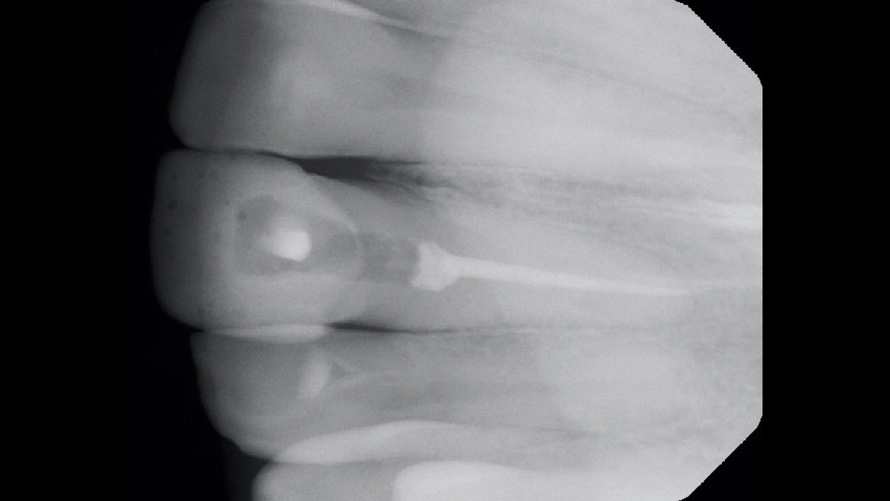

(3.) Case 1: Preoperative radiograph of the maxillary right central incisor, demonstrating periapical radiolucency and porous core buildup.

Figure 3

In the first case, the patient reported a history that included childhood dental trauma without swelling or discomfort. The intraoral examination indicated that the existing all-ceramic restoration on tooth No. 8 possessed an inappropriate morphology, surface topography, and shade. Radiographically, tooth No. 8 exhibited a large underlying resin core with significant porosity and periapical radiolucency (Figure 3). The diagnosis for tooth No. 8 was pulp necrosis with asymptomatic apical periodontitis.